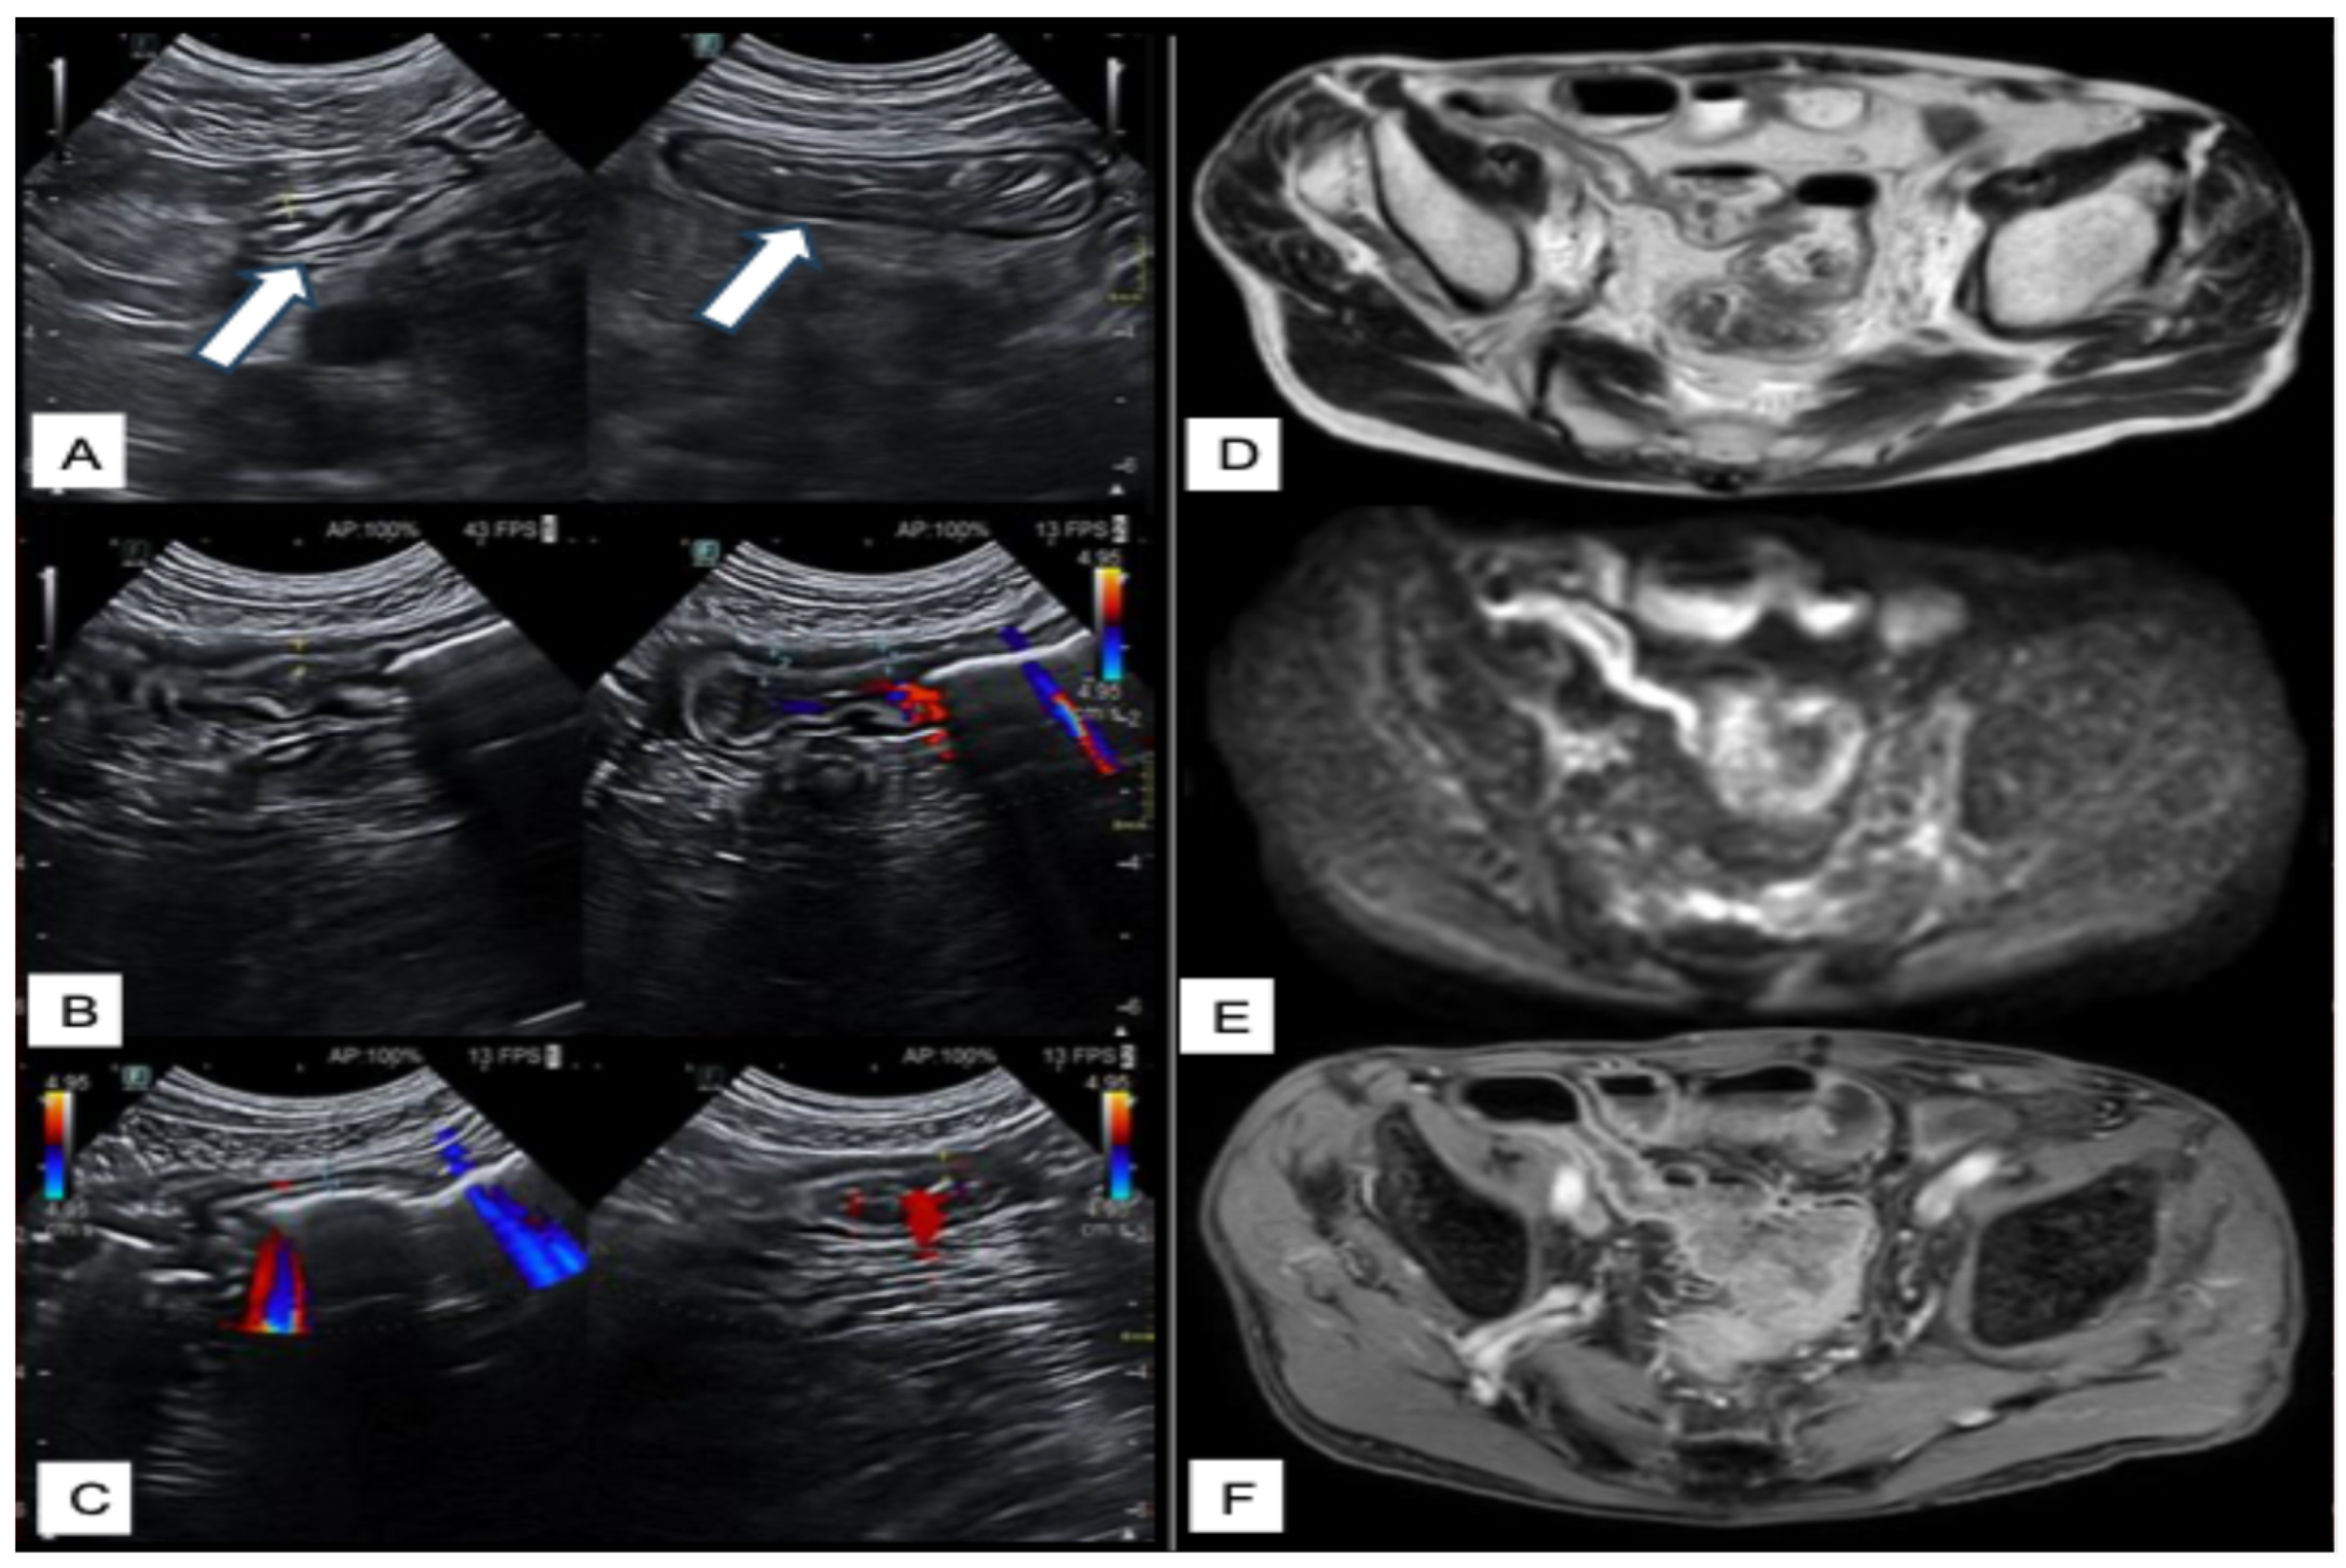

Intestinal Ultrasounds Imaging Findings and Scoring Systems

- Celikyay, F.; Yuksekkaya, R.; Yuksekkaya, M.; Kefeli, A. Color Doppler Ultrasound Assessment of Clinical Activity in Inflammatory Bowel Disease. Curr. Med. Imaging 2021, 17, 741–750. [Google Scholar] [CrossRef]

- Ripollés, T.; Martínez-Pérez, M.J.; Blanc, E.; Delgado, F.; Vizuete, J.; Paredes, J.M.; Vilar, J. Contrast-enhanced ultrasound (CEUS) in Crohn’s disease: Technique, image interpretation and clinical applications. Insights Imaging 2011, 2, 639–652. [Google Scholar] [CrossRef]